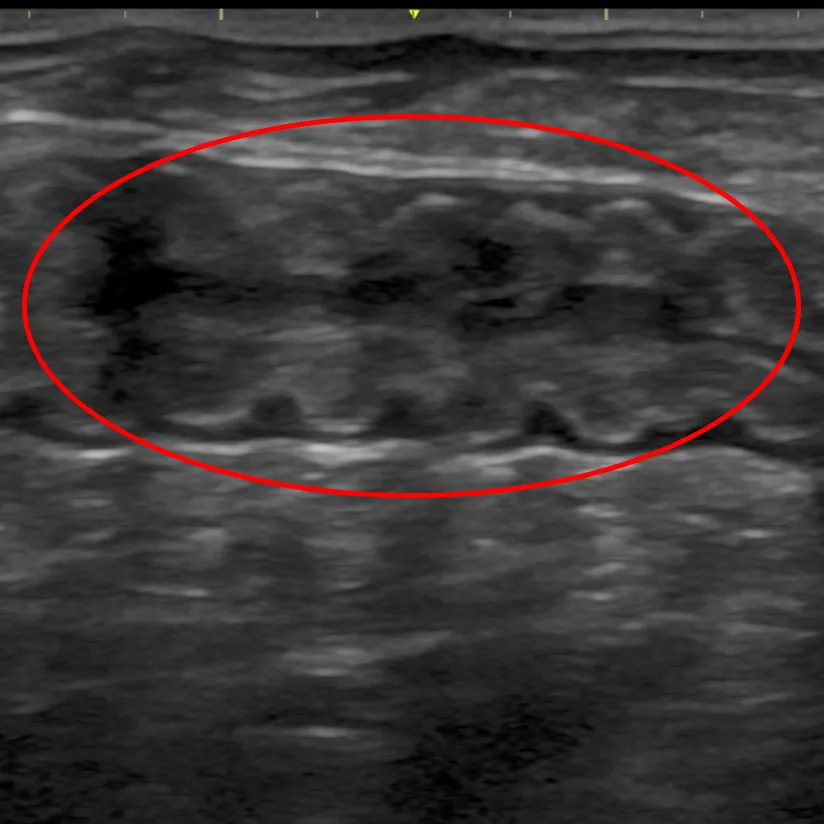

具体的には、糞便検査で感染症(寄生虫、細菌、ウィルスなど)の有無を、血液検査でスクリーニングをかけ内分泌疾患(ホルモン病)やその他の疾患を除外そして画像検査(レントゲン検査・エコー検査)で異物の誤飲、胃腸の動きや構造の変化などを確認します。

試験的治療で改善しない場合や、一般検査で異常があり追加検査が必要な場合などに精密検査を行います。例えば、エコー検査で腹腔内腫瘤があれば細胞診を、エコー検査では評価できない場合はCT検査を行います。